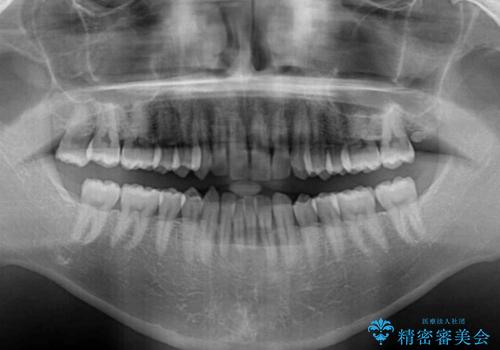

- 前歯のデコボコを気にして来院された患者様です。

インビザラインによるマウスピース矯正も適用となる歯列でしたが、できる限り自己管理の煩わしさのない状態で治したいとのことで、ワイヤー装置にて矯正治療を行うこととしました。

予定していた期間より長くかかりましたが、1年強できれいな歯列に仕上がりました。

- 症状により、抜歯が必要な場合があります